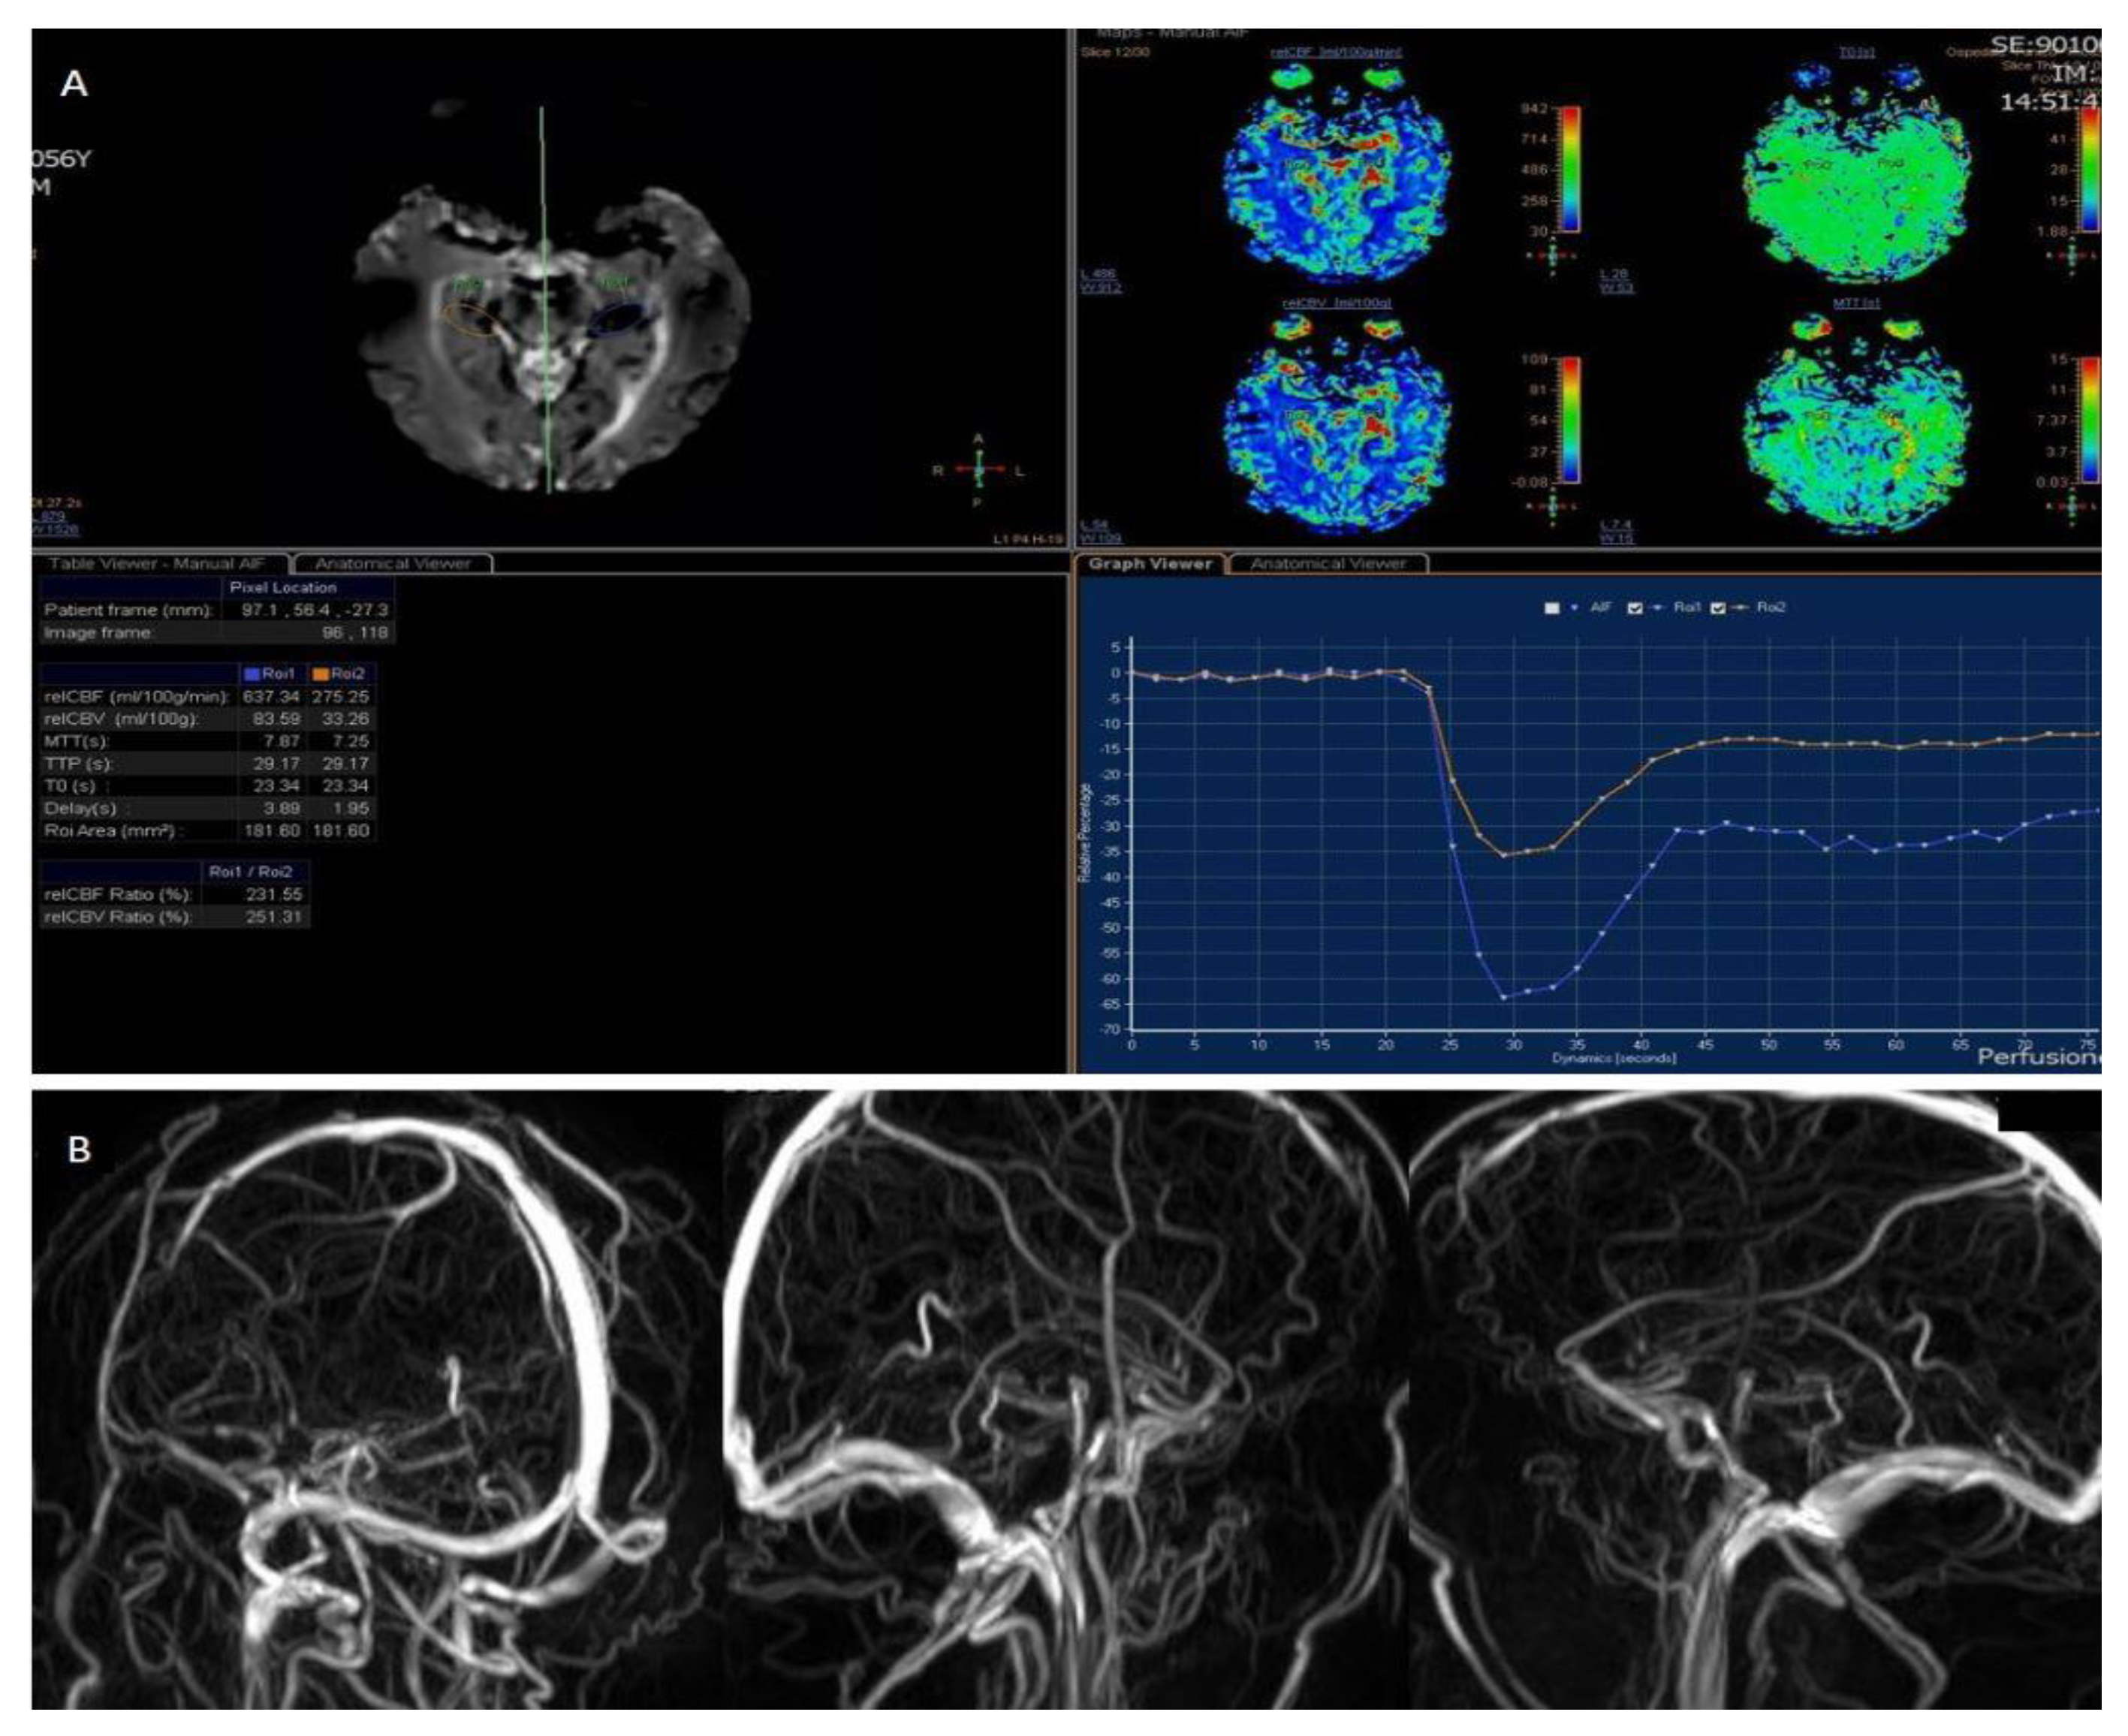

Perfusion weighted imaging executed using (A) Contrast Enhanced perfusion MRI (CEpMRI) revealed low levels of Cerebral Blood Flow (CBF, 275.25 mL/100 g/min) and Cerebral Blood Volume (CBV, 33.26 mL/100 g) in affected areas, compared to contralateral ones. (B) Phase Contrast Angiography (PCA)-MRA 3D Venography shows partial obliteration of straight sinus and lack of opacification of the vein of Galeno. CVT is a rare but considerable cause of stroke. It affects all ages but there is an increased incidence in older and young adults. The women-to-men ratio is 2.9–1.2. Some studies have shown rare cases of CVT related to COVID-19 infection and also to vaccination against it, in particular after ChAdOx1 nCoV-19 vaccine (AstraZeneca, Cambridge, UK); 1 of these was a multicentre cohort study which involved 43 hospitals across the UK [1]. Thromboembolic complications have been reported also in hospitalized patients with COVID-19, with a rate of 21–32%, due to a hypercoagulable state in those patients [2]. The most common clinical features of CVT are headache, papilledema, focal motor or sensory deficits and seizures [3]. There have been reported numerous causes of CVT, that can be categorized in infectious and non-infectious. Infectious causes include septic cranial trauma, meningitis, cerebritis, septicemia, otitis and sinusitis; among the non-infective aetiologies, malignancies, red cell and platelet disorders, coagulopathies and inflammatory disease deserve some recognition [4]. Symptoms and signs of CVT can be varied and not always typical. Neuroimaging tools play an important role in diagnosing CVT and therefore also in ensuring a timely therapeutic intervention [5].